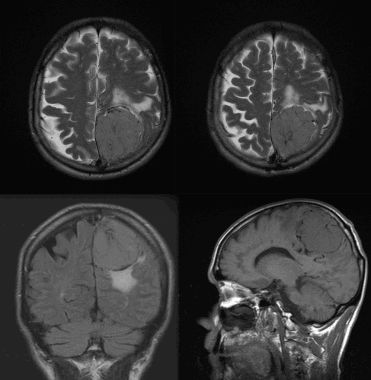

(Слева) МРТ Т1ВИ FS с КУ, аксиальная проекция. Крупная, накаливающая контраст опухоль правого сонного пространства, смещающая сонную артерию кпереди. Обратите внимание, что участки выпадения сигнала отсутствуют. Этот признак помогает дифференцировать менингиому от более распространенной опухоли-параганглиомы.

(Справа) МРТ Т1ВИ FS с КУ, коронарная проекция, тот же пациент. Крупная менингиома сонного пространства, исходящая из яремного отверстия. Обратите внимание, что в полости черепа имеется «хвост» из твердой мозговой оболочки -достаточно частая находка у пациентов, у которых менингиома основания черепа распространяется интракраниально.

(Справа) МРТ Т1ВИ FS с КУ, аксиальная проекция. Менингиома яремного отверстия распространяется вниз, в сонное пространство. Обратите внимание, что сонная артерия расположена спереди от опухоли. Подобные опухоли происходят из клеток арахноидального эндотелия. Увеличиваясь в размерах, менингиома начинает спускаться в сонное пространство. (Слева) МРТ Т1ВИ FS с КУ, аксиальная проекция. Крупная, накаливающая контраст опухоль правого сонного пространства, смещающая сонную артерию кпереди. Обратите внимание, что участки выпадения сигнала отсутствуют. Этот признак помогает дифференцировать менингиому от более распространенной опухоли-параганглиомы.